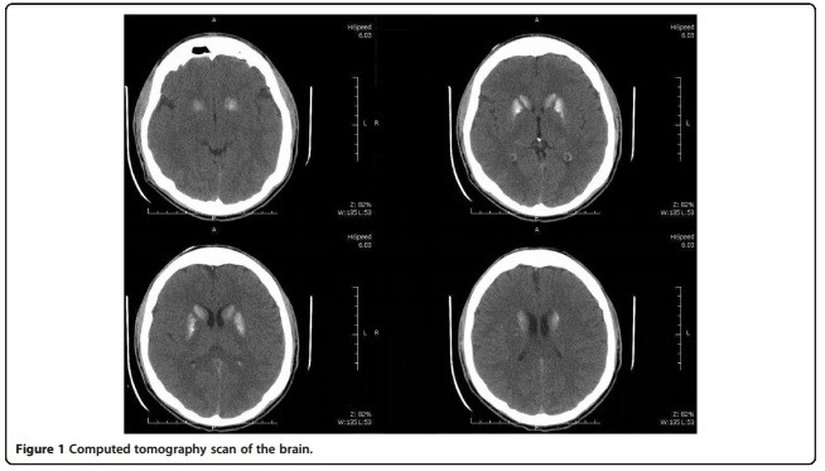

- Bilgisayarlı tomografi: beynin orta kısmında bulunan bazal ganglionda magnezyum[1] birikmesi

Beyinde magnezyum birikmesi, kalp atışında ritm bozukluğu, ayaklarda titreme gibi belirtiler arasında doğrudan bir ilişkinin bulunduğundan yola çıkan ve böylece gencin yakındığı rahatsızlığı hipo paratiroidizm olarak adlandıran doktorlar, vücutta magnezyum ve kalsiyum miktarını ayarlayan paratiroid hormonunun (PTH) kanda düşük seviyelerde olması halinde bu hastalığın ortaya çıkabileceği sonucuna varıyorlar.